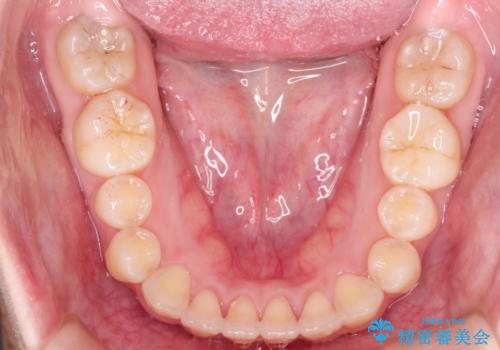

前歯にがたつきがあり、上下の歯が咬み合っていない状態でした。

歯列の横幅をひろげるのと、歯と歯の間をわずかに削ることにより、前歯のがたつきと、開咬を改善しました。